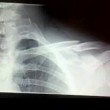

A dare la notizia dell’ infortunio è stato lo stesso Bastianich, che su Facebook ha pubblicato la radiografia della clavicola, aggiungendo: “Epic crash”, e ringraziando i medici dell’ospedale di Udine che lo hanno curato.